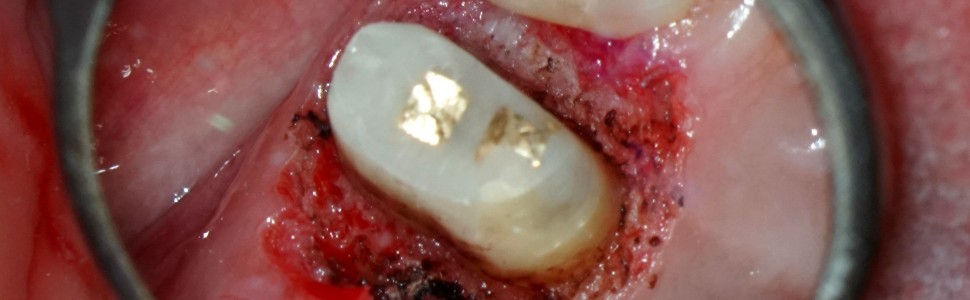

Biorąc pod uwagę powyższe, trudności należałoby spodziewać się już na etapie usuwania wypełnienia w postaci zniszczenia tkanek chorobą próchnicową poniżej poziomu dziąsła (ryc. 3). W klasycznym podejściu dokonując gingiwektomii, mógłby pojawić się problem z kontrolą krwawienia i izolacją ubytku, co skutkowałoby koniecznością tymczasowego zaopatrzenia ubytku do następnej sesji i wygojenia dziąsła, generując przejściowy defekt estetyczny oraz zwiększając dodatkowo ryzyko urazu mechanicznego znacząco już osłabionego zęba.

3

Ryc. 3. Stan po częściowym usunięciu wypełnienia kompozytowego; widoczna próchnica wtórna.